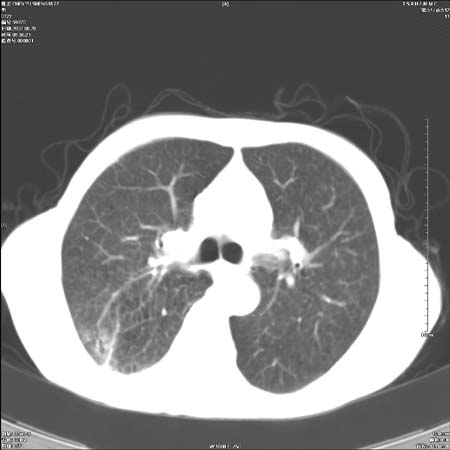

男性,72岁,既往肺结核,今复查。无前片对比。

右侧中央型肺癌伴中叶不张可能性大,建议增强扫描.右上肺陈旧性肺结核.慢性支气管炎伴肺气肿.右侧少量胸腔积液.

右侧中央型肺癌伴中叶不张可能性大,建议纤支镜检查.右上肺陈旧性肺结核.肺气肿。

典型右肺中心型肺癌

右侧中央型肺癌伴肺不张可能性大,建议增强扫描.右上肺陈旧性肺结核.慢性支气管炎伴肺气肿.右侧少量胸腔积液.

右肺中心型肺癌

右侧中央型肺癌.上肺陈旧性肺结核.

1右侧中央型肺癌伴中叶不张2右侧少量胸腔积液3右上肺陈旧性肺结核

1.右肺中心性肺癌并右肺中叶综合征2。右侧胸腔少量积液3。右肺上叶结核球已钙化,4。慢支伴肺气肿

右侧中央型肺癌伴中叶不张可能性大,建议纤支镜检查.右上肺陈旧性肺结核.肺气肿。

右侧中央型肺癌伴中叶不张可能性大,建议增强扫描.右上肺陈旧性肺结核.慢性支气管炎伴肺气肿.右侧少量胸腔积液.

右侧中央型肺癌伴中叶不张

右肺中央型肺癌伴右肺中叶不张。

右上肺陈旧性肺结核。

支持右肺中心型肺癌并中叶不张,右上肺陈旧性肺结核钙化,右侧少量胸腔积液。

支持右侧中央型肺癌伴中叶不张可能性大,建议增强扫描.右上肺陈旧性肺结核.慢性支气管炎伴肺气肿.右侧少量胸腔积液.

支持 1右侧中心型肺癌伴中叶不张2右侧少量胸腔积液3右上肺陈旧性肺结核4双肺局限性肺气肿

1,右侧中央型肺癌.

2,右上肺陈旧性肺结核.

1.右侧中央型肺癌伴中叶不张,建议纤支镜检查.

2.右上肺陈旧性肺结核.

3.肺气肿。

4.右侧少量胸腔积液.

右侧中央型肺癌伴中叶不张并纵隔淋巴结增大,建议增强扫描.右上肺陈旧性肺结核.慢性支气管炎伴肺气肿.右侧少量胸腔积液。

右肺中心型肺癌并肺不张,陈旧性肺tb.慢支,肺气肿.

陈旧性肺结核.慢性支气管炎伴肺气肿,中央型肺癌伴中叶不张。

右侧中央型肺癌伴中叶不张可能性大;右上肺陈旧性肺结核.慢性支气管炎伴肺气肿

陈旧性结核是存在,但真正致命的却是右侧中心型肺癌。